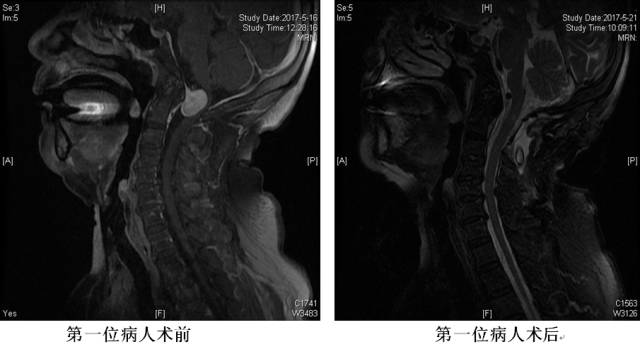

脊柱外科跨越手术禁区

枕颈交界硬膜内肿瘤由于位置特殊,位于脑干延髓和脊髓的交界,周围有双侧的椎动脉以及颅底神经和C1-2脊神经分支,以往多为手术治疗的禁区。

近日,青大附院脊柱外科市南病区收治2例此类患者,皆因肿瘤体积大、位置特殊、风险高等原因多家求治未果,慕名求诊于青大附院。脊柱外科充分多次会诊,充分准备,成功将肿瘤完整切除。术中患者生命体征平稳,术后1周康复出院,恢复良好。